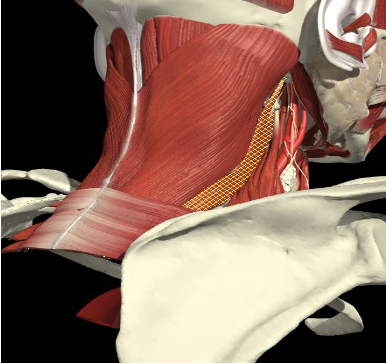

Levator Scapulae

Origin

First to the fourth cervical vertebrae.

Insertion

Medial edge of the scapula, between the superior angle and the root of the spine.

Action

- Acts as a checkrein for the bent head

Levator Scapulae & Neck Motion

Left Lateral Flexion

Left U Trapezius, SCapitus and Levator Scapulae

Left U Trapezius,

Right SCapitus , Levator Scapulae

Bilateral U Trapezius

Scapitus, Levator Scapulae

Right Rotation

Extension

Posterior Surface Anatomy

- Line from acromium to midline and inferior

- Feel the edge of the spine

- Above and below is infra and supraspinatus fossae

- Follow spine to midline (T3 level)

- Above that along the medial border

6. Line obliquely from there to transverse process of C1-4 (below and anterior to splenius capitus)